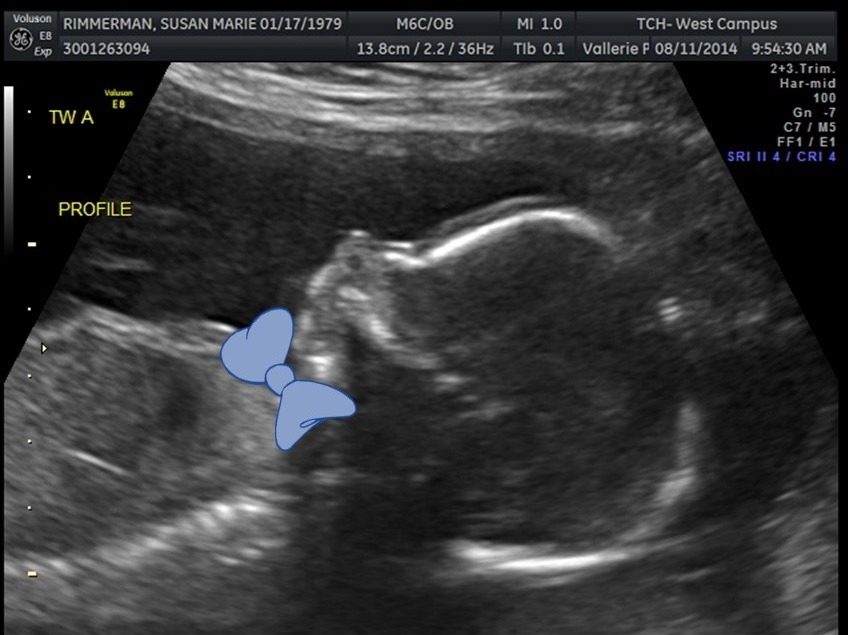

Was your guess correct! August 16, 2014 By srimmerman We are super excited to share what baby Rimm A and baby Rimm B are! Both boys are happy and healthy! Baby RImm A is 12oz and Baby Rimm B is 11oz. They are both VERY active and I’m sure going to be giving us a run for our money once they are born!! Share this: Share on X (Opens in new window) X Share on Facebook (Opens in new window) Facebook Like Loading... Related